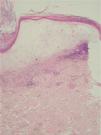

A la exploración física se objetivó la presencia de placas blanquecinas de superficie atrófica con tapones foliculares y bordes eritematosos dispuestos de forma lineal a lo largo de la zona superior derecha de la espalda (fig. 1), así como lesiones más aisladas en la zona infraclavicular derecha. En el flanco derecho se apreciaba la presencia también de placas hipopigmentadas e induradas sobre un área deprimida con hiperpigmentación postinflamatoria correspondiente a los dermatomas D9-D10, zona en la que había sufrido un episodio de herpes zóster 7 años antes (fig. 2). El estudio histopatológico de una biopsia extraída de las lesiones en el hombro derecho mostró la presencia de adelgazamiento de la epidermis con pérdida de las crestas epidérmicas, marcado edema en la dermis papilar, homogeneización del colágeno y un infiltrado linfocitario en la dermis media (fig. 3). Tras la confirmación histopatológica de liquen escleroso y atrófico se prescribió tratamiento tópico con propionato de clobetasol al 0,05 %, con mejoría moderada de las lesiones tras un mes de tratamiento.